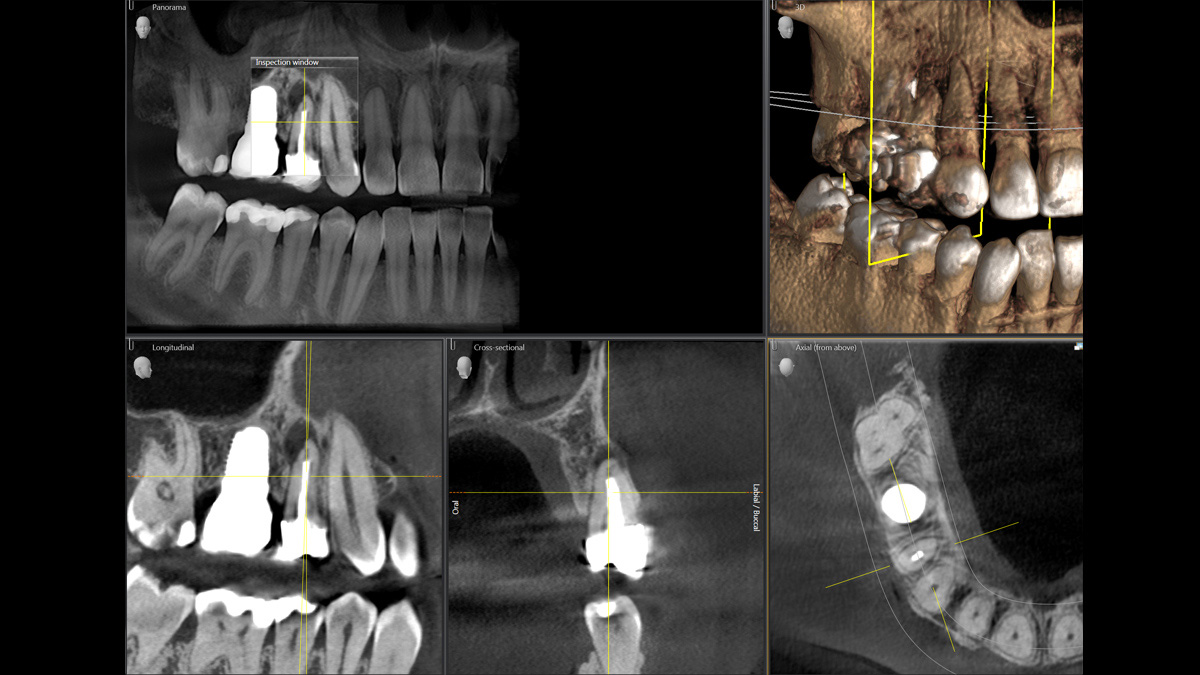

Mit dem Low Dose-Modus erhalten Sie 3D-Bilder im Dosisbereich einer 2D-Röntgenaufnahme. Im HD-Modus werden während eines einzelnen Umlaufs mehr als 800 Einzelbilder aufgenommen und zu einem 3D-Volumen mit bis zu 80 μm zusammengeführt. Der Vorteil für Sie: rauschärmere Aufnahmen in hoher Auflösung

Nicht nur wegen meines Interesses an Technik finde ich die Kombination aus Direktumwandlung und rekonstruktivem Autofokus im Orthophos SL wirklich spannend. Die daraus resultierenden präzisen Bilder eignen sich hervorragend für die Interpretation. In Kombination mit der Volumenauswahl in 3D haben wir einen universell einsetzbaren Diagnostikpartner für unsere Praxis.“

Marcin Wojtunik, Facharzt für Mundchirurgie, Pfronten, Deutschland

Ein breites Spektrum an Volumengrößen für verschiedene diagnostische und klinische Anforderungen von Ø 5 × 5,5 cm bis Ø 11 × 10 cm